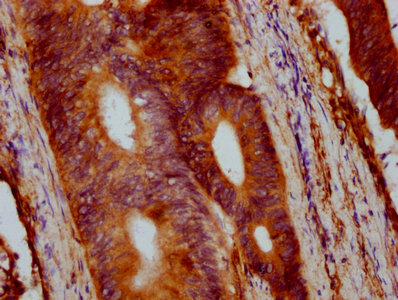

IHC image of CSB-PA029544EA01HU diluted at 1:400 and staining in paraffin-embedded human colon cancer performed on a Leica BondTM system. After dewaxing and hydration, antigen retrieval was mediated by high pressure in a citrate buffer (pH 6.0). Section was blocked with 10% normal goat serum 30min at RT. Then primary antibody (1% BSA) was incubated at 4°C overnight. The primary is detected by a biotinylated secondary antibody and visualized using an HRP conjugated SP system.